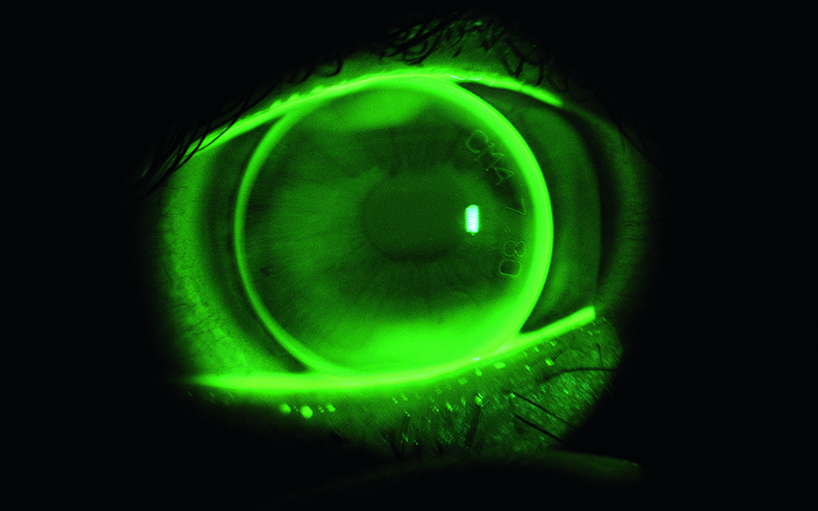

• DCT-Lens

Développement d’une lentille de contact spéciale qui contient un capteur de pression pour la détermination de la pression oculaire.